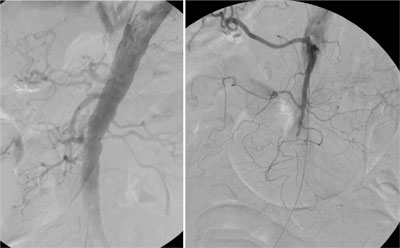

Paciente de 84 anos, sexo feminino, hipertensa, portadora de fibrilação atrial crônica e marcapasso definitivo associado a insuficiência coronariana. Procurou atendimento por apresentar forte dor abdominal em cólica, iniciada há poucas horas e que não cessou com uso de analgésicos tradicionais. Ao exame físico, observou-se ritmo cardíaco irregular por fibrilação atrial crônica e dor abdominal difusa à palpação profunda, sem sinais de descompressão dolorosa do abdome. Indicado estudo angiográfico realizado cerca de 3 horas do inicio da dor, que demonstrou oclusão do terço médio da artéria mesentérica superior. Realizado tratamento endovascular, mediante trombólise mecânica associada ao implante de stent em estenose localizada no terço médio da artéria mesentérica superior, sem intercorrências. Paciente permaneceu internada em Unidade de Terapia Intensiva, encontrando-se hemodinamicamente estável no primeiro dia após o procedimento. Entretanto, como os padrões laboratoriais de acidose metabólica e leucocitose com desvio à esquerda permanecessem, foi submetida à laparotomia exploradora sendo encontrado segmento cianótico, sendo optado preventivamente por ressecção de 70 cm de intestino delgado à 2m do ângulo de Treitz sem intercorrências. Após melhora dos padrões clínicos e laboratoriais, recebeu alta da UTI, permanecendo internada no mesmo Hospital. No 10 dia pós operatório a paciente apresentava desconforto abdominal, sendo realizado nova arteriografia que mostrava a perviedade da artéria mesentérica superior. No trigésimo dia pós operatório a paciente se alimentava e apresentava evacuações normalmente mas mantinha desconforto abdominal e leucocitose. Foi submetida a uma nova laparotomia sem achados de isquemia ou de infecção na cavidade.